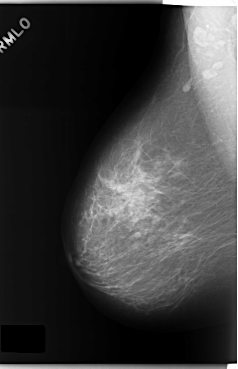

ics_version 1.0 filename C-0173-1 DATE_OF_STUDY 8 7 1996 PATIENT_AGE 67 FILM FILM_TYPE REGULAR DENSITY 2 DATE_DIGITIZED 12 3 1998 DIGITIZER LUMISYS LASER SEQUENCE LEFT_CC LINES 5936 PIXELS_PER_LINE 3688 BITS_PER_PIXEL 12 RESOLUTION 50 OVERLAY LEFT_MLO LINES 5880 PIXELS_PER_LINE 3552 BITS_PER_PIXEL 12 RESOLUTION 50 OVERLAY RIGHT_CC LINES 5872 PIXELS_PER_LINE 3752 BITS_PER_PIXEL 12 RESOLUTION 50 NON_OVERLAY RIGHT_MLO LINES 5896 PIXELS_PER_LINE 3808 BITS_PER_PIXEL 12 RESOLUTION 50 NON_OVERLAY |